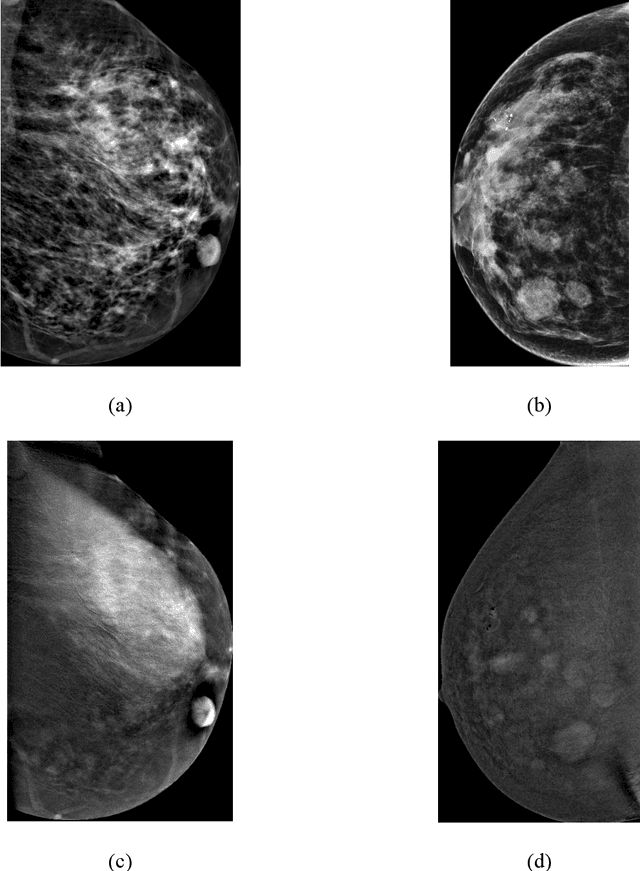

Abstract:That datasets that are used in todays research are especially vast in the medical field. Different types of medical images such as X-rays, MRI, CT scan etc. take up large amounts of space. This volume of data introduces challenges like accessing and retrieving specific images due to the size of the database. An efficient image retrieval system is essential as the database continues to grow to save time and resources. In this paper, we propose an approach to medical image retrieval using DenseNet for feature extraction and use FAISS for similarity search. DenseNet is well-suited for feature extraction in complex medical images and FAISS enables efficient handling of high-dimensional data in large-scale datasets. Unlike existing methods focused solely on classification accuracy, our method prioritizes both retrieval speed and diagnostic relevance, addressing a critical gap in real-time case comparison for radiologists. We applied the classification of breast cancer images using the BIRADS system. We utilized DenseNet's powerful feature representation and FAISSs efficient indexing capabilities to achieve high precision and recall in retrieving relevant images for diagnosis. We experimented on a dataset of 2006 images from the Categorized Digital Database for Low Energy and Subtracted Contrast Enhanced Spectral Mammography (CDD-CESM) images available on The Cancer Imaging Archive (TCIA). Our method outperforms conventional retrieval techniques, achieving a precision of 80% at k=5 for BIRADS classification. The dataset includes annotated CESM images and medical reports, providing a comprehensive foundation for our research.